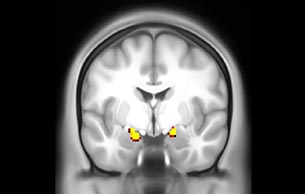

Measuring and filtering out physiological noise in fMRI

Physiological noise is an important source of unexplained variation in fMRI analyses. With MultiBand SENSE, sampling rates below one second become feasible. This allows for capturing cardiac and respiratory signals. These can be automatically determined and then filtered out using independent component analysis [6].

The fMRI pulse sequence was a single shot FFE echo planar acquisition using MultiBand SENSE factor 5, dS SENSE factor 1.25, isotropic voxel size 2.7 mm, 50 transverse slices, TR 700 ms, TE 30 ms, flip angle 52 degrees, 765 dynamic scans, total scan duration 9:01 minutes. Image provided by Matthan Caan, PhD, Assistant Professor at the AMC.

Resting state fMRI

Imaging was performed using Ingenia 3T CX with a 32ch dS Head coil, TR 1.6 sec, TE 35 ms, voxel size 3.1 x 3.1 x 3.1 mm, 46 slices and Multiband SENSE factor 2. Image provided by Dr. Gispert

Default mode network as discovered by resting state fMRI in one participant of the ALFA cohort [7]. rs-fMRI allows us to find networks of brain regions with highly correlated activity and sustaining distinct brain functions. The default mode network (in warm color scale) is active when the brain is focused on introspective thinking and has been shown to be altered in Alzheimer’s. Interestingly, brain areas of this network are known to show abnormal levels of one of the pathological hallmarks of Alzheimer’s (b-amyloid deposition) in preclinical stages. We want to better understand the alterations of these brain networks in preclinical stages of Alzheimer's and explore their potential use as biomarkers.